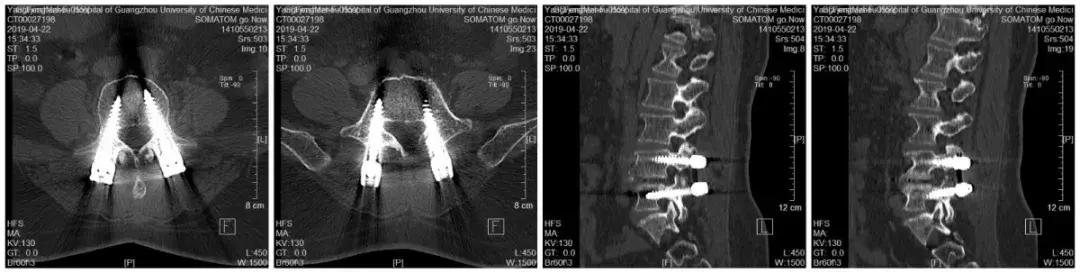

3、手术治疗:对于椎管狭窄的治疗是针对脊柱骨骼结构的治疗。

1)手术指征:症状较重者,经过半年以上非手术治疗无效,影响正常生活和工作。或有明确的神经传导障碍,尤其是某些肌肉无力和萎缩。

2)椎板切除、神经根减压是基本的手术方式。